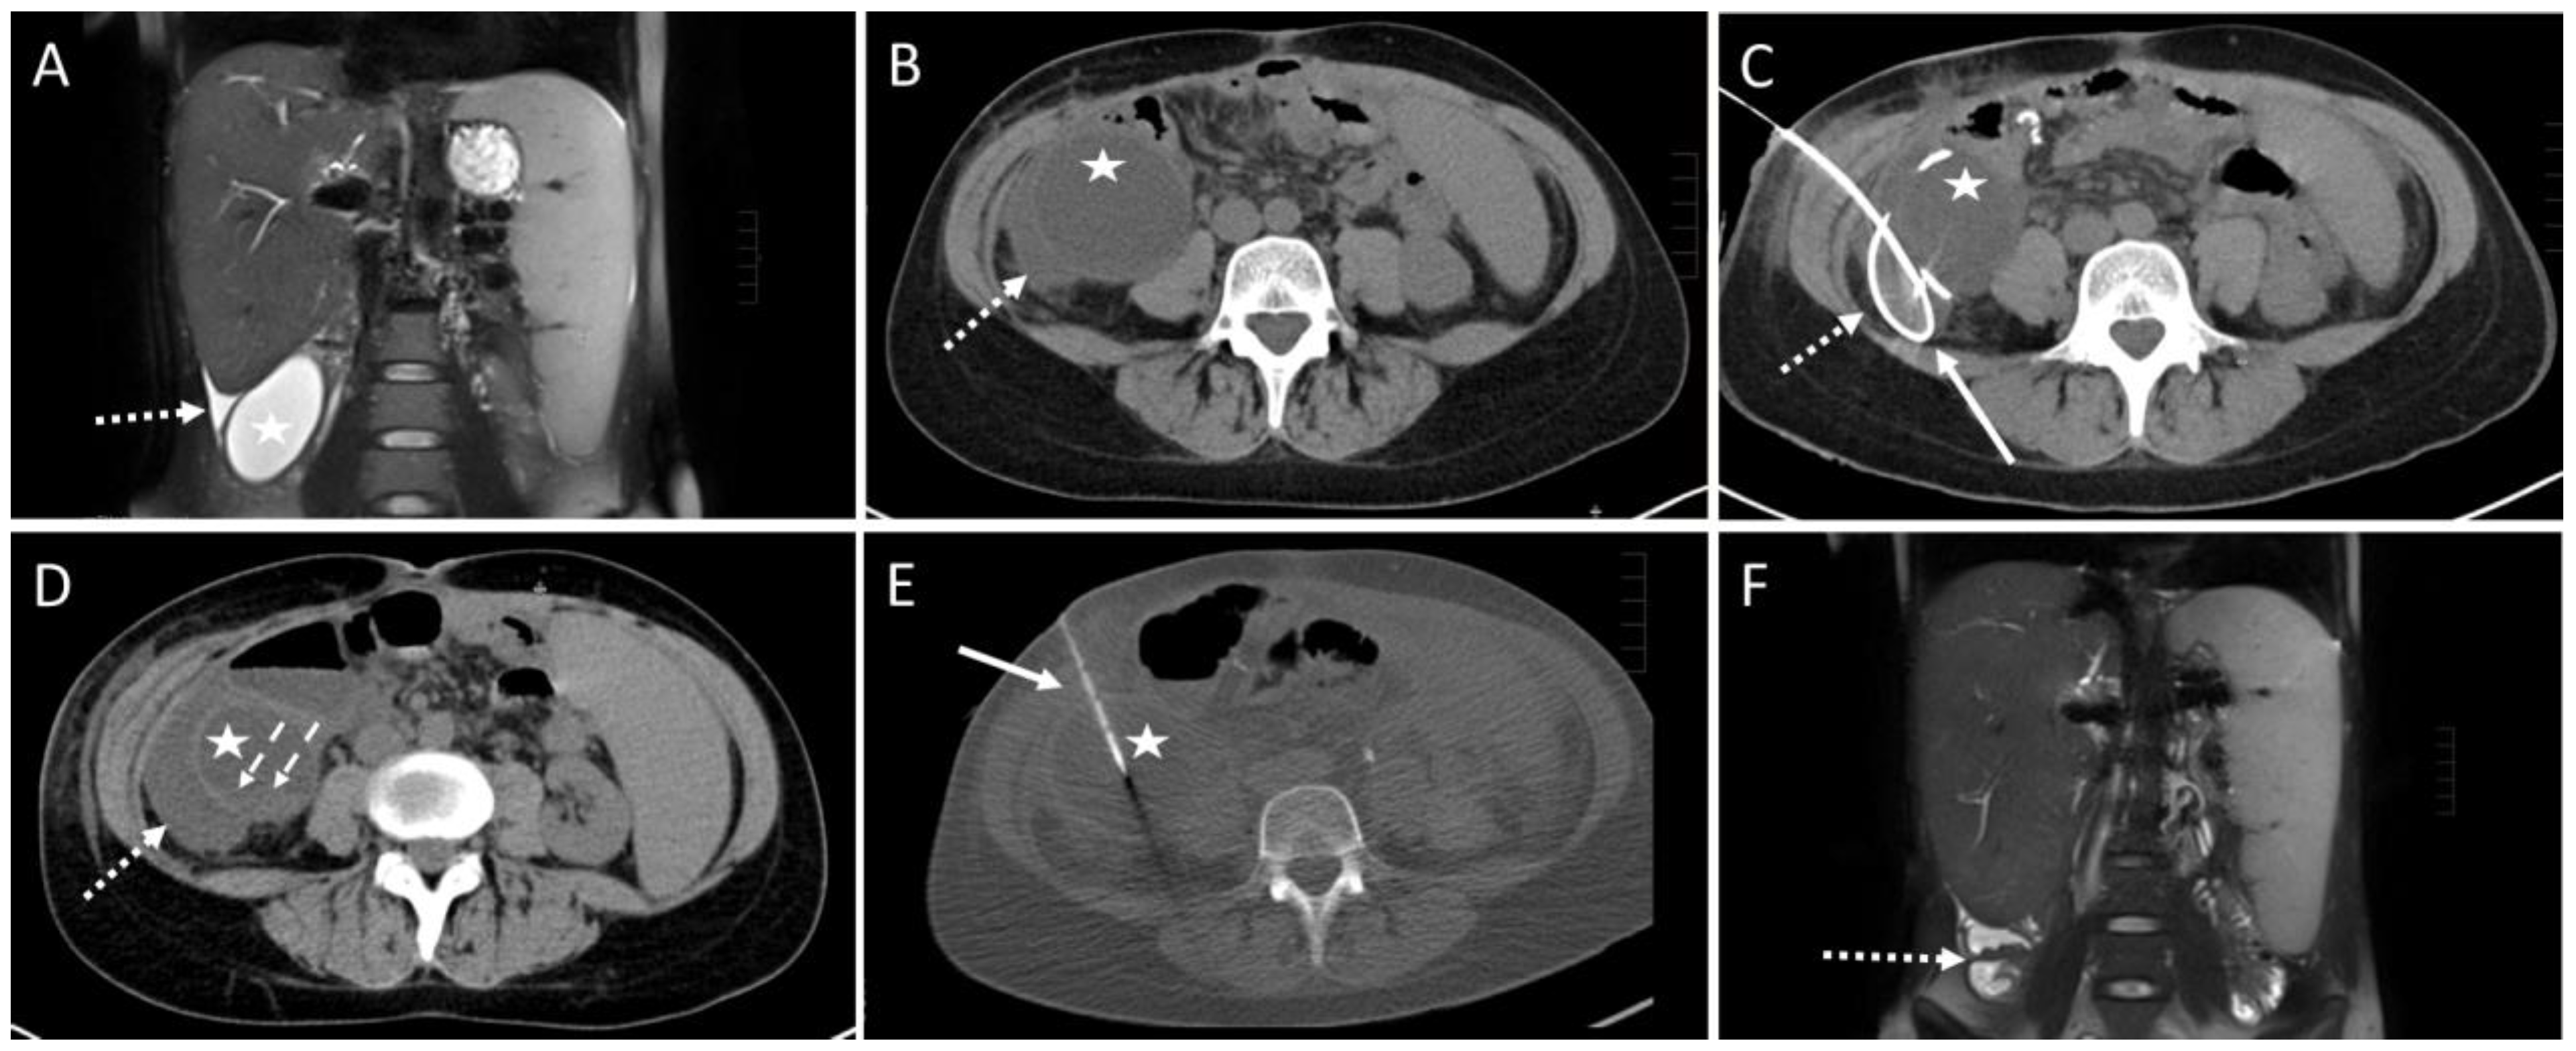

Figure 4. Example of a CT-guided drainage placement with significant complications following SIR guidelines. A 47-year-old male with history of liver transplantation due to alcoholic cirrhosis. After six weeks, an increase in inflammatory parameters was observed. (A) CT planning scan 52 days after transplantation: a fluid collection (arrowheads; density: 6 Hounsfield units (HU)) encompassing the bypass (dotted arrow) between right common iliac artery and hepatic artery in the right paracolic gutter. (B) Using lateral access via the retrocolic space, a 10F pigtail drainage (solid arrow) is placed under CT fluoroscopy. Dotted arrow: drainage trajectory anterior to the bypass. (C) After removal of the Trocar, a correct position of the drain (solid arrow) was shown. Several milliliters of serous fluid could be aspirated. Dotted arrow: bypass. (D) An unenhanced CT control scan revealed increased density (30 HU; compare to figure (A)) of the fluid collection (arrowheads) in the right paracolic gutter suspicious of acute bleeding. Dotted arrow: bypass. (E) Enhanced follow up CT scan 10 min after drain placement shows contrast agent extravasation (dashed arrow) originating from a branch of the right colic artery. Due to the arterial contrasting, the bypass (dotted arrow) is now clearly delineated. Arrowheads: fluid collection. (F) Coronary maximum-intensity projection (40 mm) showed an intact, inconspicuous bypass (dotted arrow). Dashed arrow: contrast agent extravasation. The injured vessel was subject to successful immediate revision surgery.